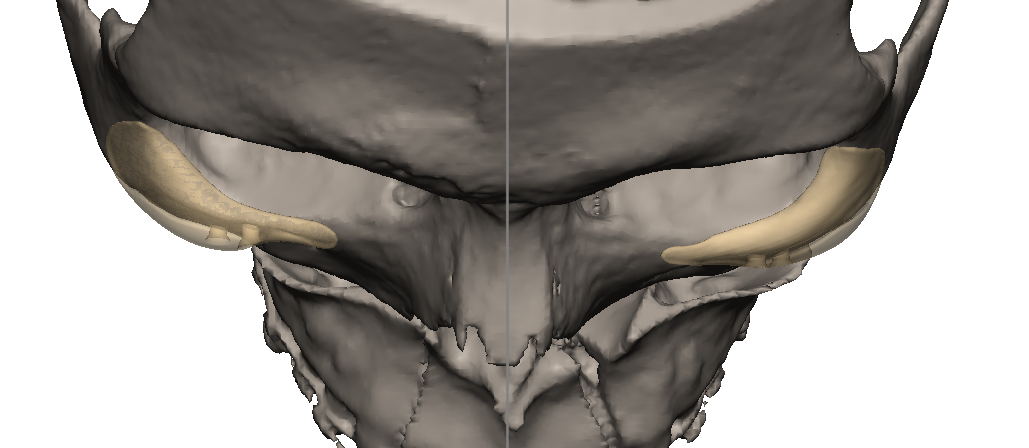

im getting surgery(trimax and infras) soon, any thoughts on this?my left side (the 31 mm) is also less wide in real life, i think would be good to extend it more to the nose area.